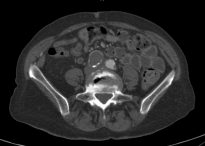

An iliac artery aneurysm is a dilatation of the iliac artery. A normal iliac artery measures up to 1 cm in diameter. An iliac artery that is wider than that is aneurysmal.

Isolated iliac artery aneurysms are uncommon. For reference, aortic aneurysms are perhaps present in 4% of people. An aneurysm in the iliac artery exists in 0.1%. These aneurysms are more common in conjunction with an aortic aneurysm. In any case, symptoms are rare. That is why diagnosis is usually incidental. Abdominal or even lumbar imaging may show this finding. The aneurysms are categorized by location: internal, external or common iliac artery. Common and external iliac artery aneurysms are actually more common than in the internal iliac artery.

Decisions of whether to treat depend on several factors. First, whether the iliac aneurysm is isolated or not. If the iliac aneurysm accompanies an aortic aneurysm a joint decision may be a way to go. This is particularly true if the aortic aneurysm is treated with a stent-graft. Then the limbs of the graft are deployed in the iliac artery and by that the aneurysm is excluded.